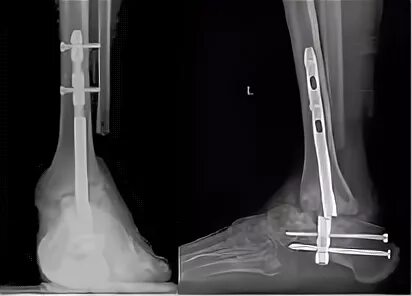

Артродез форум